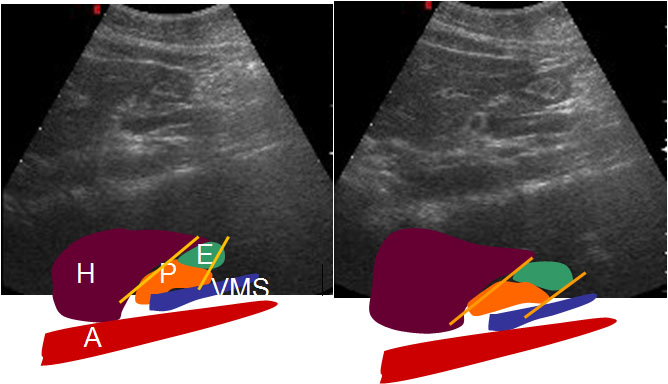

SIGNO DEL DESPLAZAMIENTO

El desplazamiento del estómago (que desciende en la inspiración) con respecto al páncreas (órgano retroperitoneal inmóvil con la respiración) es un hallazgo normal. Éste, pues, es uno de los pocos signos radiológicos que representan un hallazgo normal.

La presencia de este signo excluye invasión pancreática en pacientes con carcinoma gástrico. Los esquemas ilustran el desplazamiento normal. H: hígado. E: estómago. P: páncreas. VMS: vena mesentérica superior. A: aorta.

Lim, HK y cols: Assessment of pancreatic invasion in patients with advanced gastric carcinoma: usefulness of the sliding sign on sonograms. AJR 1999; 172: 615-618.